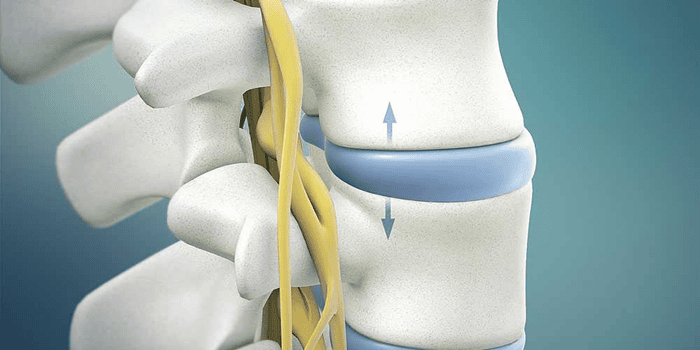

جراحی لیزری دیسک کمر (PLDD) با هدف درمان فتق دیسکها به عنوان یک روش عمل بسته معرفی شده است که با استفاده از گرما، فشار داخلی دیسک را کاهش میدهد. در این روش کمتهاجمی، پس از بیحسی موضعی و بدون نیاز به بیهوشی عمومی، سوزن باریکی با هدایت رادیوگرافی وارد دیسک فتقیافته میشود.

سپس فیبر نوری حامل اشعه لیزر، بخش کوچکی از هسته ژلهای دیسک را تبخیر میکند. این تبخیر آب دیسک که میتواند حدود ۵۷ درصد از فشار دیسک را کاهش دهد، یک خلأ نسبی ایجاد کرده و باعث میشود مواد بیرونزده دیسک به سمت داخل کشیده شوند.

نتیجه این کاهش فشار بر ریشههای عصبی، تسکین فوری درد سیاتیک است. مزیتهای کلیدی این تکنیک شامل: ریسک پایین عفونت، کاهش خونریزی و مهمتر از همه، دوره نقاهت بسیار کوتاه (معمولاً کمتر از ۶ هفته) در مقایسه با جراحی باز سنتی (۳ تا ۶ ماه) است که امکان بازگشت سریع بیمار به فعالیتهای روزمره را فراهم میسازد.